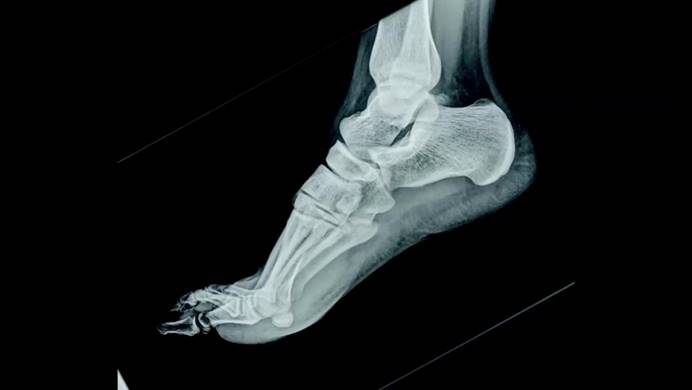

微小細節往往是正確診斷的關鍵。在事故及緊急情況下,高質量X射線圖像對患者至關重要,這就是為什么AGFA對其生產的設備要求特別嚴格。借助蔡司解決方案不僅獲得高質量及可靠的檢測結果,測量時間更是降低了90%。

為數字X射線成像技術制造光盤時,面臨的挑戰之一就是光盤的平面度,越理想的光盤平面越可以確保呈現的圖像可靠詳細。光盤的質量會影響圖像呈現的信息,圖像里的模糊區域會使得診斷變得更加困難,在極端情況下,醫生可能會看不到骨折和腫瘤,存在潛在風險。

▌高質量X射線圖像